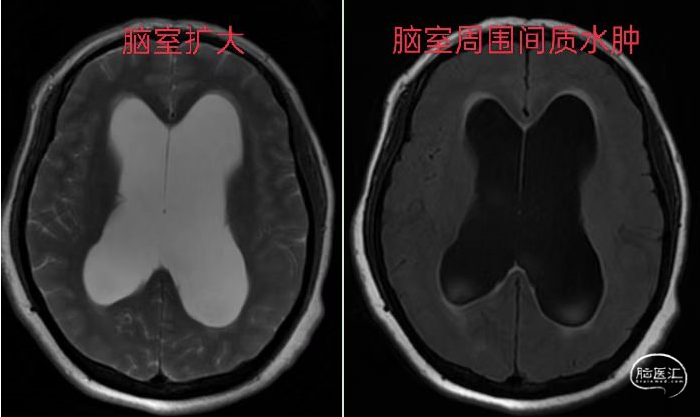

患者梁某,女性,52岁,长期的脑积水造成患者步态不稳、认知障碍、尿失禁,严重影响患者生活。于2022年9月9日以“行走不稳伴尿失禁半年”入院,头颅MRI检查提示“脑室系统扩大,双侧脑室额角周围间质水肿”。

为进一步鉴别脑积水类型,行磁共振3D FIESTA序列检查可见三脑室、侧脑室扩大明显,中脑导水管中段及下口阻塞、三脑室底受压下陷,诊断梗阻性脑积水。